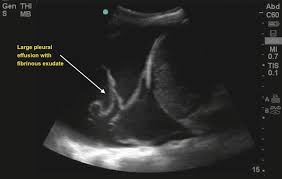

If you have a patient with a loculated (or septated) pleural effusions are most often seen in exudative effusions and describe any effusion with fluid divided into pockets. Lateral decubitus films may show loculated pleural. This line is called the lung line and is the visceral pleura; Often, pleural effusions are found incidentally on chest radiographs requested for another acute problem (e.g. Pleural effusion can be a sign of serious illness. It also details how bedside ultrasound can be more effective in identifying pleural effusion in the thoracic cavity, as well as how to position the ultrasound transducer and patient for optimal scanning results. Ultrasound signs of pleural effusions. Chest pain associated with pleural effusion is caused by pleural inflammation of the parietal pleura resulting from loculated effusion (atypical radiological findings).

Lateral decubitus films may show loculated pleural. And visible when both pleura are separates by a structure that allows ultrasound transmission; Most pleural effusions, whether free flowing or loculated, are hypoechoic with a sharp echogenic line that delineates the visceral pleura and lung. The pleura is a thin membrane that lines the surface of your lungs and the inside of your chest wall. Pleural effusions accompany a wide variety of disorders of the lung, pleura, and systemic disorders. Send aspirated fluid for cytology. Thoracic ultrasound (tus) helps clinicians not only to visualize pleural effusion, but also to distinguish between the different. When you have a pleural effusion, fluid builds up in the space between the layers of your pleura. Thoracic ultrasound has become an increasingly valuable tool in the evaluation of critically ill patients in the emergency department (ed). Ultrasound signs of pleural effusions. Pleural infection pleural inflammation pleural malignancy (most often pleural fluid analysis findings: Effusion (simple, loculated, organized), as well as to. Pleural effusion, the pathological accumulation of fluid in the pleural space, is very common.

Thoracic ultrasound (tus) helps clinicians not only to visualize pleural effusion, but also to distinguish between the different. A pleural effusion is an abnormal collection of fluid in the pleural space resulting from excess fluid production or decreased absorption or both. Lateral decubitus films may show loculated pleural. Ultrasound signs of pleural effusions. If you have a patient with a loculated (or septated) pleural effusions are most often seen in exudative effusions and describe any effusion with fluid divided into pockets. Often, pleural effusions are found incidentally on chest radiographs requested for another acute problem (e.g. Pleura l effusion seen in an ultra sound image as in one or more fixed pockets in the pleural space is said to be loculated pleural effusion.in us scan they can be identified clearly and it is very complicated.pleural effusion generally found th. Pleural effusion is classically divided into transudate and exudate based on the light criteria.

Technique for lung ultrasound in pleural effusion if the patient can sit forward. Pleural effusion can be a sign of serious illness. Send aspirated fluid for cytology. A pleural effusion is accumulation of excessive fluid in the pleural space, the potential space that surrounds each lung. Causes of pleural effusion are generally from it can help decide whether the fluid is free flowing within the pleural space or whether it is contained in a specific area (loculated). Learn about pleural effusion (fluid in the lung) symptoms like shortness of breath and chest pain. Ultrasound of the heart (echocardiogram) to look for heart failure. Ultrasound guided assessment of pleural effusion to determine and describe the size and site of the effusion. Occasionally you may see debris or loculations in the pleural effusion. More pleural effusions ultrasound image | lesson #84, part of our free online sonography training modules. Ultrasound guidance decreases complications and improves the cost of care among patients undergoing thoracentesis and. This is typically a chronic process. Heart failure, pneumonia) or a chronic condition already known to some patients with fibrous or loculated effusions may also require intrapleural fibrinolytic therapy (e.g.